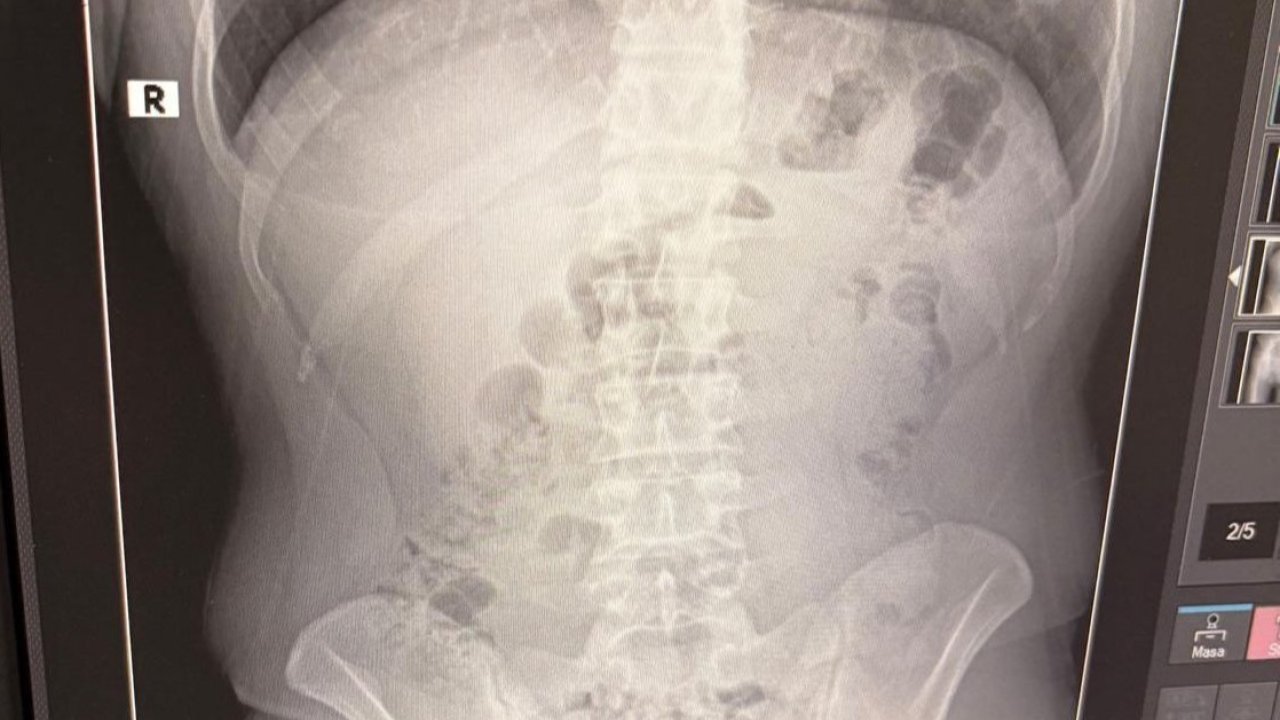

Uşak'ta uyuşturucu ticareti yaptıkları iddiasıyla yakalanan İran uyruklu 3 şahsın evinde ve midelerinde kapsüller içine gizlenmiş halde toplam 1 kilo 516 gram metamfetamin ele geçirildi.Uşak İl Emniyet Müdürlüğü Narkotik Suçlarla Mücadele Şube Müdürlüğü ekipleri, İran'dan Türkiye'ye uyuşturucu madde getirildiği yönündeki istihbarat üzerine çalışma başlattı. Yapılan teknik ve fiziki takip sonucunda, İran'dan İzmir Adnan Menderes Havalimanı'na gelen ve buradan ticari taksiyle Uşak'a geçtiği belirlenen Y.T., A.T. ve M.J., Kurtuluş Mahallesi'nde tespit edilen adreste yakalandı.Adreste yapılan arama sırasında ekipler, şüphelilerden birinin üstünde 1 adet kapsül ele geçirdi. Şüphe üzerine tüm şüpheliler hastaneye götürüldü ve yapılan röntgen kontrollerinde 3 kişinin midelerinde kapsül içine gizlenmiş metamfetamin tespit edildi.Hastanede tedavi altına alınan şüphelilerin vücudundan kapsüller çıkarılırken, adreste ele geçirilenlerle birlikte toplam 1 kilo 516 gram metamfetamin ele geçirildi.Ele geçirilen maddelere el konulurken, şüpheliler emniyetteki işlemlerinin ardından adliyeye sevk edildi. Çıkarıldıkları mahkemece tutuklanan Y.T., A.T. ve M.J. cezaevine gönderildi.